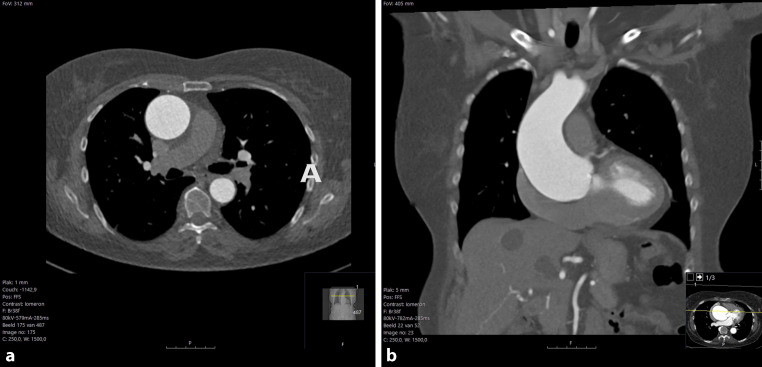

Sudden onset chest pain after a CT-scan of the aorta.